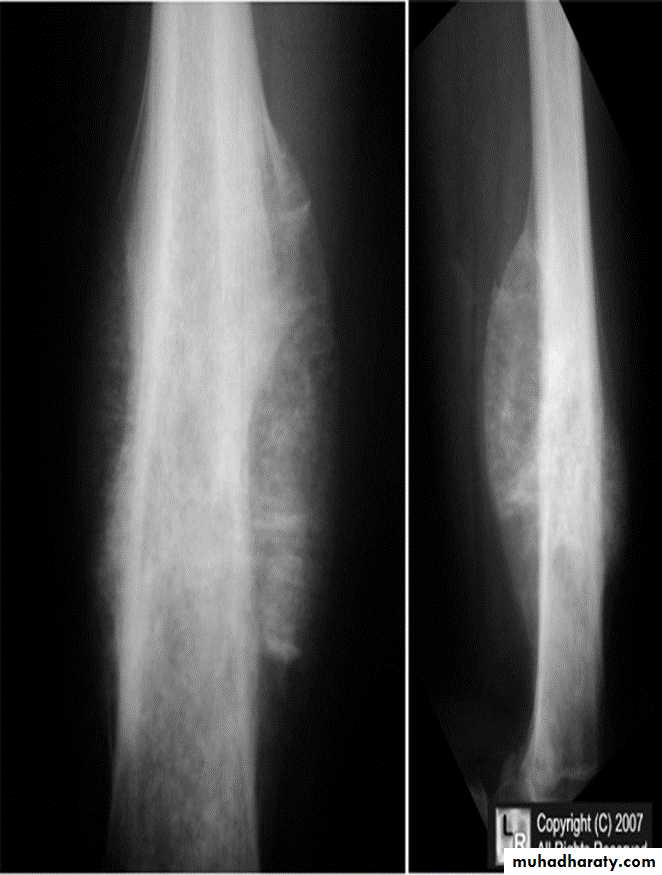

Ewings Sarcoma

Highly malignant with tendency to metastasize.Age: children.

Site: shaft of long bone.

Findings:

ill-defined destruction with onion peal periosteal reaction.

Ewing's sarcoma. Sunray speculation Onion peel appearance